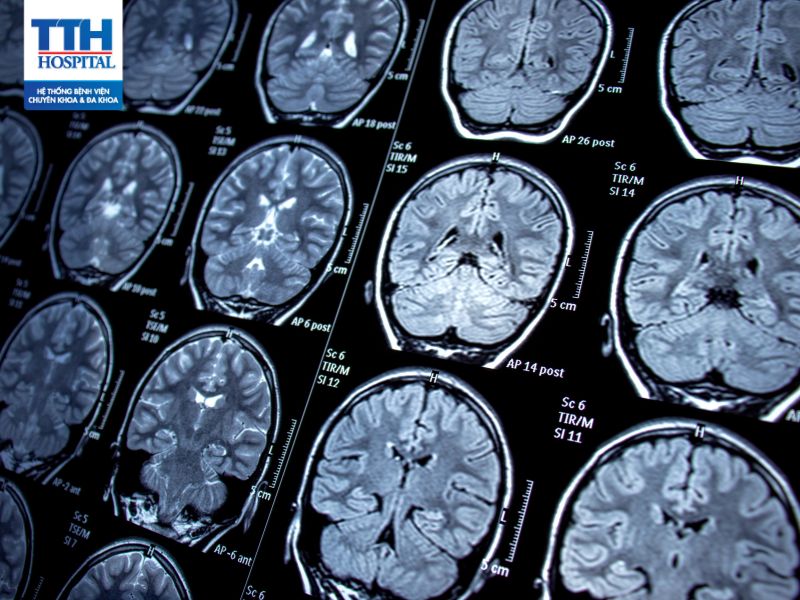

Chụp cộng hưởng từ (MRI) và CT (CT scan)

Giúp xác định các tác nhân gây ra động kinh như khối u não, tổn thương não, hoặc các vấn đề cơ bản khác.